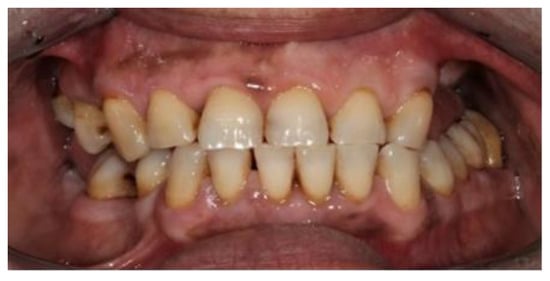

2. Case Report

The subject involved in this clinical study was a healthy woman, 54 years old. The request of this patient was to improve her mouth both functionally and aesthetically, which was altered because of the partial edentulism (Kennedy Class II). She asked to avoid any invasive surgery. During the anamnesis, she declared not to be affected by any systemic pathology (e.g., diabetes, hypercholesterolemia or hypertension). She also declared not to be affected by an allergy to any medication or similar drugs; she declared not to be subjected to any pharmacologic treatment except some analgesic therapy to treat sporadic headaches. The patient claimed to smoke 20 cigarettes a day for more than 20 years. The next step was to perform an objective examination, associated with a series of intraoral pictures (Figure 1, Figure 2, Figure 3, Figure 4 and Figure 5) and to the analysis of a radiographic exam (orthopantomography, Figure 6) that was acquired 10 months earlier when the same subject underwent the therapy and the teeth extraction 4.7–4.8. The objective examination showed poor oral hygiene, with plaque accumulation as well as the presence of many pigmentations due to excessive smoking. The radiography showed bilateral bone atrophy together with periodontal damage for most of the residual dental elements. These conditions represented a limitation to the insertion of implants for a fixed prosthesis.

During the fifth appointment, both the prostheses were delivered without having to do any retouching (Figure 19 and Figure 20), and the following clinical evaluations were performed:

The tests described above made possible the evaluation of the precision of both the products, even if the outcome measurements are not quantifiable. Both products have proved to be extremely accurate. Moreover, the patient was asked to use both prostheses for a week, during which she did not notice any difference between the two. The patient was satisfied with both the products, which she declared to be extremely comfortable.

Figure 1. Frontal view.